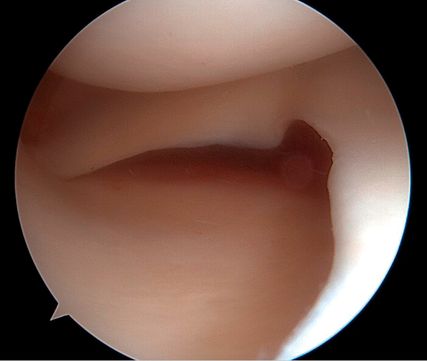

Arthroskopische Instabilitätszeichen: „floating meniscus“ und „drive-through sign“

In einer Level-I-Studie an Patient:innen mit kombinierten VKB- und Grad-II-MCL-Verletzungen (nach Fetto und Marshall) und „Floating-Meniskus-Zeichen“ zeigte die Patientengruppe nach MCL-Augmentation mittels gestielter autologer Gracilis-Sehne signifikant weniger VKB-Revisionen, eine geringere residuale MCL-Laxität sowie bessere patient:innenberichtete Outcome-Scores nach 24 Monaten im Vergleich zu Patient:innen mit isolierter VKB-Rekonstruktion und konservativ behandeltem MCL. Die Abbildung 1 zeigt das „Floating-Meniskus-Zeichen“, ein arthroskopisches Zeichen der medialen Instabilität, bei dem sich der mediale Meniskus vom tibialen Plateau abhebt, infolge einer meniskotibialen Läsion des tiefen Innenbandes. Aufgrund einer zusätzlichen Läsion des oberflächlichen Längsbandes kommt es zu einer medialen Gelenköffnung, die als „medial drive-through sign“ bezeichnet wird.

Flache dMCL- und sMCL-Rekonstruktion

Biomechanische Untersuchungen haben gezeigt, dass eine flache MCL-Rekonstruktionstechnik der klassischen Einzelbündeltechnik hinsichtlich der Wiederherstellung der physiologischen Kniekinematik überlegen ist, und sie wird von den Autoren insbesondere bei höhergradigen Verletzungen bevorzugt. Für diese Technik können ein Peroneus-longus-Split-Autograft, die Semitendinosussehne (bevorzugt aus dem kontralateralen Bein) oder verschiedene Allografts verwendet werden. Der tubuläre Anteil der Sehne wird hierzu durch eine longitudinale Halbierung und anschließendes Abflachen mit einer Raspel zu einem flachen Transplantat präpariert.2 Die detaillierte Beschreibung der Operationstechnik ist ebenfalls über einen QR-Code als Videoanleitung verfügbar (Abb.4).